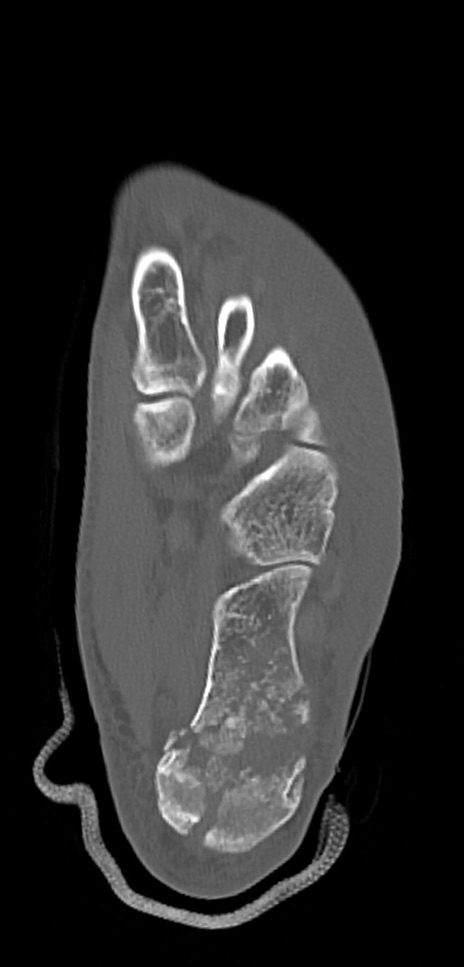

症例37 左足関節CT(横断像)

左足関節CT